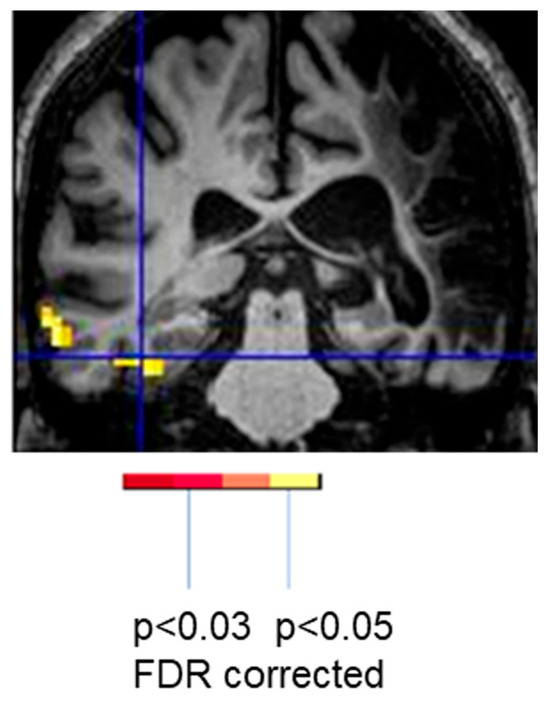

- Kleiser, R.; Wittsack, H.-J.; Bütefisch, C.M.; Jörgens, S.; Seitz, R.J. Functional Activation within the PI-DWI Mismatch Region in Recovery from Ischemic Stroke: Preliminary Observations. Neuroimage 2005, 24, 515–523. [Google Scholar] [CrossRef] [PubMed]

- Purcell, J.; Sebastian, R.; Leigh, R.; Jarso, S.; Davis, C.; Posner, J.; Wright, A.; Hillis, A.E. Recovery of Orthographic Processing after Stroke: A Longitudinal FMRI Study. Cortex 2017, 92, 103–118. [Google Scholar] [CrossRef] [PubMed]